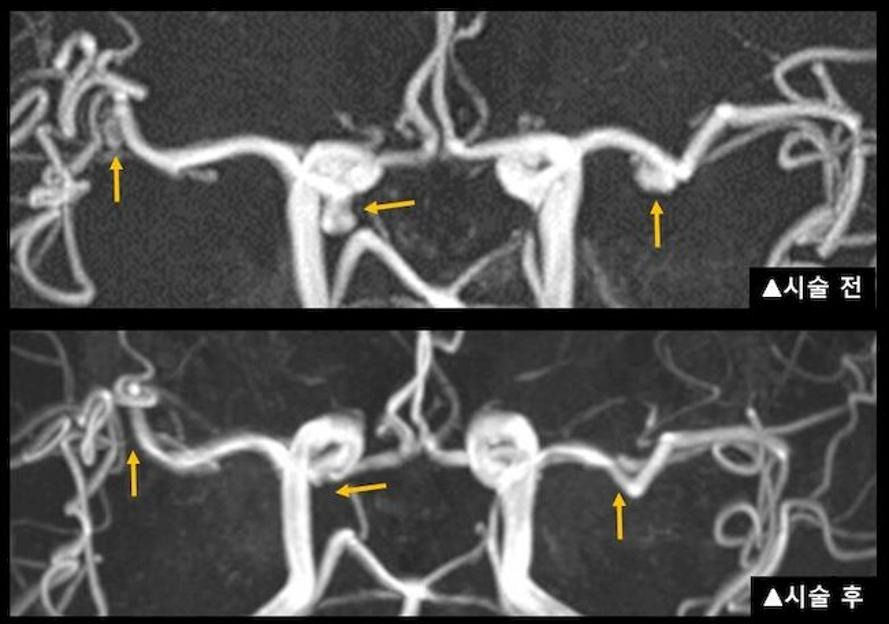

혈관 내 코일 색전술

이 방법은 허벅지나 손목의 동맥을 통해 카테터를 삽입하여 동맥류 내부에 백금 코일을 채워 혈류를 차단하는 최소 침습적 시술입니다. 이 시술은 개두술에 비해 회복이 빠르고 입원 기간이 짧습니다. 일반적으로 입원 기간은 2~4일이며, 시술 후 빠른 일상생활 복귀가 가능합니다. 그러나 재발 가능성이 있어 정기적인 추적 검사가 필요할 수 있습니다.